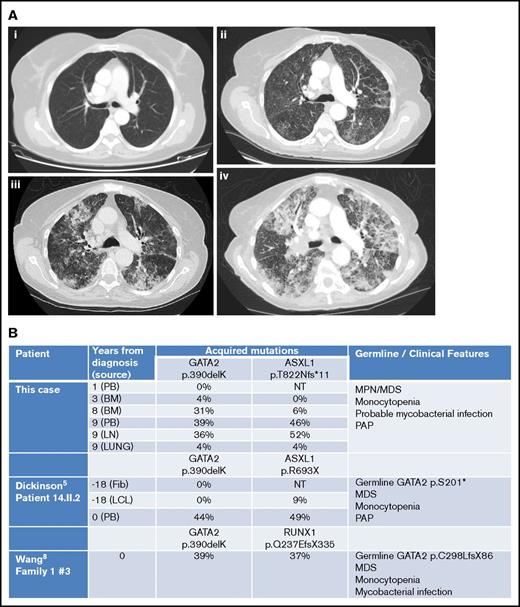

However, by then, she reported weight loss, worsening cough with breathlessness, and dystrophic nails consistent with fungal infection. Chest computed tomography revealed progressive changes with interstitial thickening and air space shadowing throughout both lungs, plus small volume necrotic mediastinal lymphadenopathy (Figure 2A). Sputum, BAL, and endobronchial ultrasound biopsies of her central lymphadenopathy were culture negative; lymph node histology showed acute necrotic changes. BAL contained branching hyphae consistent with Aspergillus species. BAL galactomannan was positive at 1.58, and voriconazole was commenced.

Imaging and molecular investigations. (A) Serial computed tomography chest images (2007-2015). (i) June 2007: no respiratory symptoms. Normal imaging. (ii) January 2015: no respiratory symptoms but evidence of progressive MPN/MDS. Early interstitial changes are present. (iii) June 2015: cough and breathlessness. Progressive interstitial changes plus air space shadowing are present. (iv) September 2015: respiratory failure secondary to PAP. “Crazy paving” changes plus consolidation characteristic of PAP visible. (B) Comparison of somatically acquired c.1168_1170delAAG p.390delK GATA2 mutations. Three patients have been reported with somatically acquired p.390delK mutation in GATA2. Germ line mutations in GATA2 and other cooperating mutations in ASXL1 or RUNX1 were also present in two previous cases. Fib, fibroblast; LCL, lymphoid cell line; LN, lymph node; NT, not tested; PB, peripheral blood.

She was investigated for the presence of GATA2 mutation. BM DNA was extracted from paraffin blocks using the QIAamp DNA FFPE Tissue Kit (56404; QIAGEN) according to the manufacturer’s instructions. Using Sanger sequencing, the patient was found to harbor a mutation in exon 8 of GATA2 (c.1168_1170delAAG; p.390delK) and a mutation of ASXL1 (c.2464_2465insA; p.T822Nfs*11). The GATA2 mutation was predicted to be disease-causing using the MutationTaster prediction program6 (Mutation Surveyor software version 4.0.8). On retrospective analysis of her previous DNA samples and estimation of variant allele frequency from electrophoretograms, this GATA2 mutation was not detected in 2006, increased in abundance from 2009 to 2015, and was only found at 4% in lung tissue in 2015, suggesting that it was an acquired somatic mutation (Figure 2B; supplemental Figures). ASXL1 mutation was observed emerging at later time points, probably as a subclone.

Somatic mutations in GATA2 occur rarely in MPN and other myeloid neoplasms,9,11-13 with the exception of MDS/AML associated with biallelic CEBPA mutations.7 Our patient had a trinucleotide deletion c.1168_1170delAAG; p390delK, identical to that previously reported as a second somatic mutation in 2 other patients with coexisting germ line GATA2 mutations (Figure 2B). In our previous patient (14.II.2),5 p390delK was confirmed as somatic by serial sampling and sequencing of fibroblast and LCL DNA. In the other reported patient, p390delK was proven to be biallelic with the germ line GATA2 mutation by TA-cloning.12 In all three, cooperating ASXL1 or RUNX1 mutations were observed at similar variant allele frequency to the somatic GATA2 variant. The present case remains unique in that an isolated somatic GATA2 mutation was responsible for the GATA2-related disease.